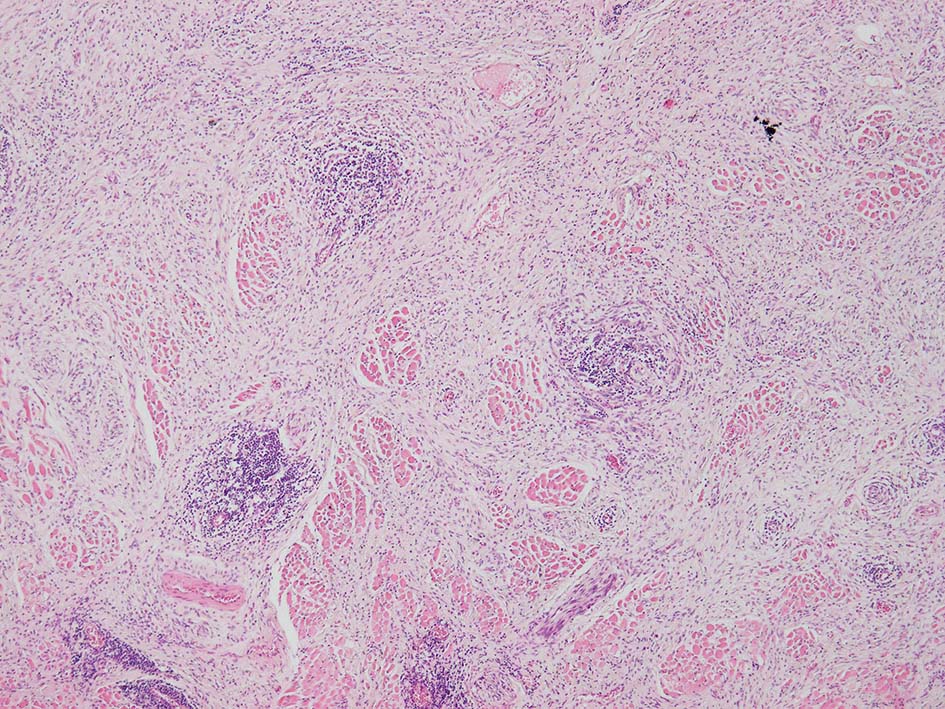

紡錘形異型メラノサイトが著明な間質反応(desmoplasia)を伴い増殖する特殊な色素性病変。*1. desmoplastic neurotropic melanomaは, desmoplastic melanomaのうち神経向性(neurotropism:神経周囲侵襲像)がめだつものでReedら*2が最初に報告した。

いずれも腫瘍細胞の異型性が乏しく, 背景の間質反応がめだつこと, メラニンの存在が目立たないことが特徴である。

再発腫瘤病変の組織像